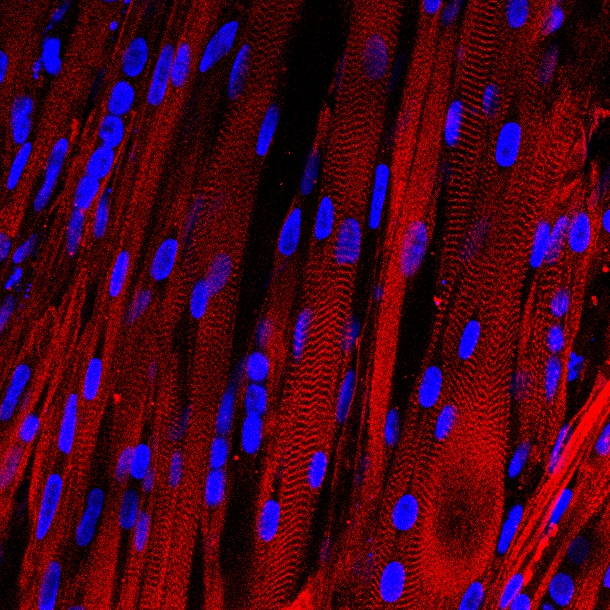

Vista microscópica de las fibras musculares humanas cultivadas en laboratorio, teñidas para mostrar los patrones que forman sus unidades musculares básicas y sus proteínas asociadas (en rojo), y que son característicos de los músculos humanos. Fuente: Universidad de Duke.